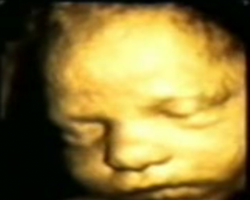

- ecografia fetală 4D ne prezinta imaginea corpului fătului aflat în uter cu mişcările pe care le are în momentul examinării.

Pentru a vedea pozele marite puneti mouse-ul in interiorul pozelor mici: